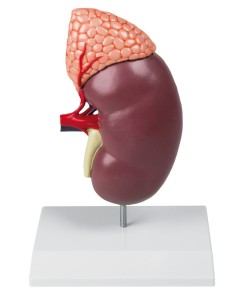

Modèle anatomique de néphron avec vaisseaux sanguins, agrandi 120 fois k10/1